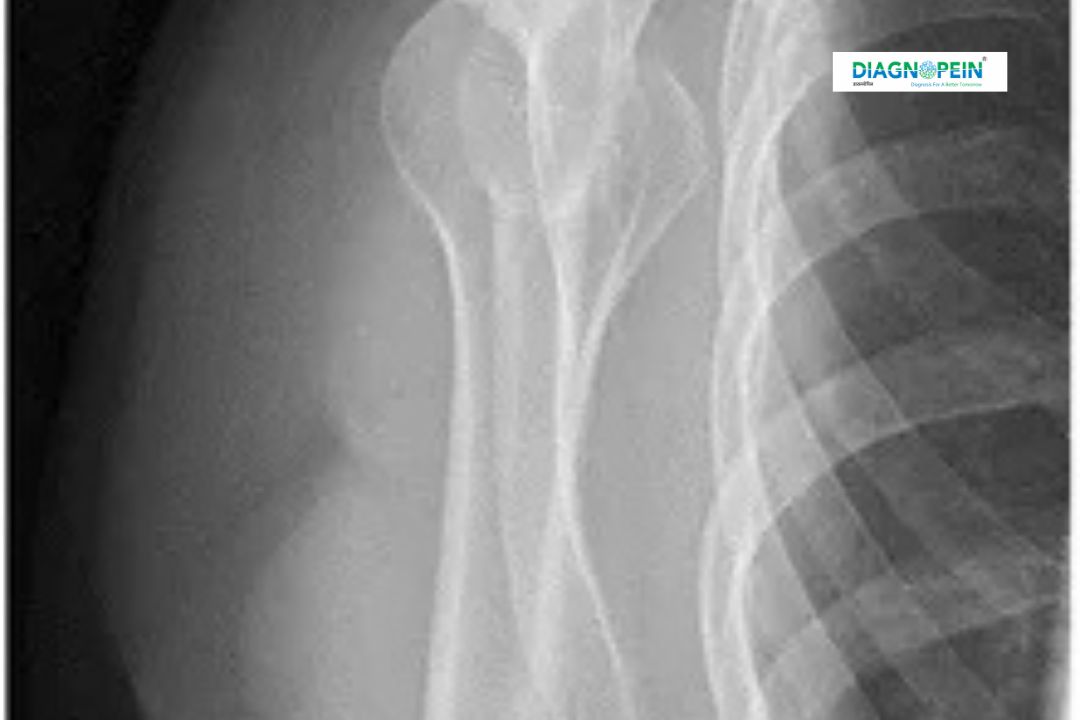

X-RAY SHOULDER AP/LAT is a commonly performed diagnostic imaging test used to evaluate the bones and joint structures of the shoulder. This examination includes two essential views—Anteroposterior (AP) and Lateral (LAT)—to provide a comprehensive assessment of the shoulder joint. At Diagnopein, X-RAY SHOULDER AP/LAT in Nashik is performed using advanced digital radiography systems to ensure accurate and high-quality imaging.

The importance of X-RAY SHOULDER AP/LAT lies in its ability to provide clear visualization of the shoulder bones, including the humerus, scapula, clavicle, and glenoid cavity. This imaging test helps doctors make timely and accurate diagnoses, especially in cases of trauma, chronic shoulder pain, or restricted movement.

By capturing both AP and Lateral views, this test minimizes the chances of missed injuries. X-RAY SHOULDER AP/LAT in Nashik is often recommended for patients involved in accidents, sports injuries, or those experiencing long-term shoulder discomfort. Early diagnosis through X-RAY SHOULDER AP/LAT helps prevent complications and supports effective treatment planning.